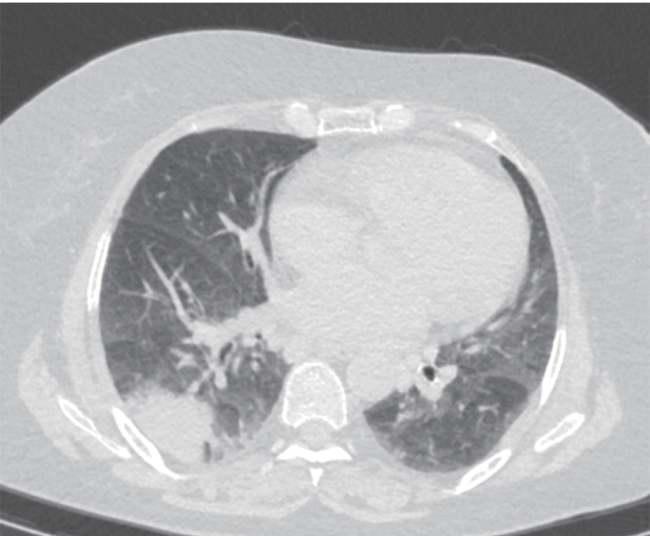

「在我们本地医院看了下一直没好,这两天有点喘不上气。听说咱这医院大,就再来看看。」患者拿出了在外院拍的片子,CT 显示双侧肺部炎症,可见支气管充气相,少量胸腔积液。主任做了个听诊,简单开了些检查,便让他下午来办住院。

胸部 CT 影像资料(图片仅作示例,非本病例资料)

图源:参考资料 5